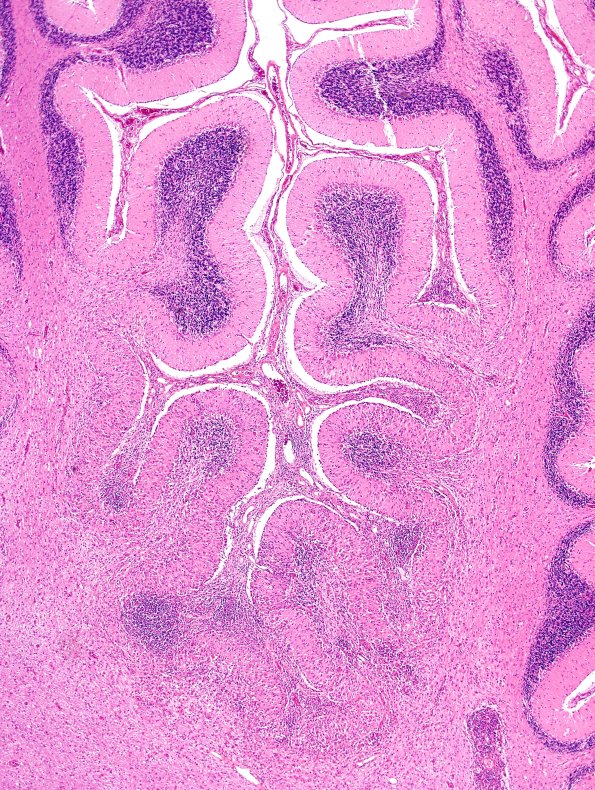

At several magnifications the significant granule and Purkinje cell loss continues to show involvement of sulcal depths. (H&E)